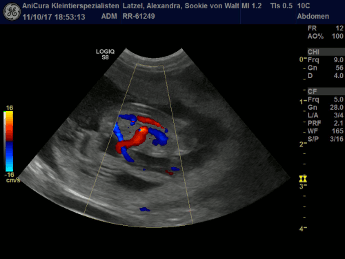

| 11.10.2017 |

| Sookie ist werdende Mami! Im Ultraschall haben wir vier Welpis gesehen! Hier die Bilder!!! |